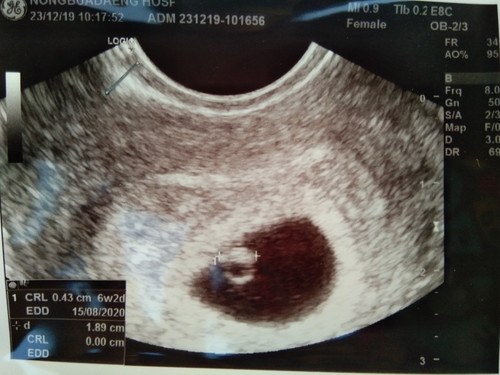

ในที่สุดก้อไปฝากท้องแล้วจ้าา แม่ๆว่า 6 สัปดาห์ เพิ่ง4 มิลเอง น้องตัวเล้กไปมั้ยค่ะ

น่าจะใกล้เคียงกันค่ะ ของเรา 6w เหมือนกันน้องแค่ 3 มิล ยังไม่ได้ยินเสียงหัวใจเพราะเล็กเกินไป (เราซาวผ่านหน้าท้องนะ)